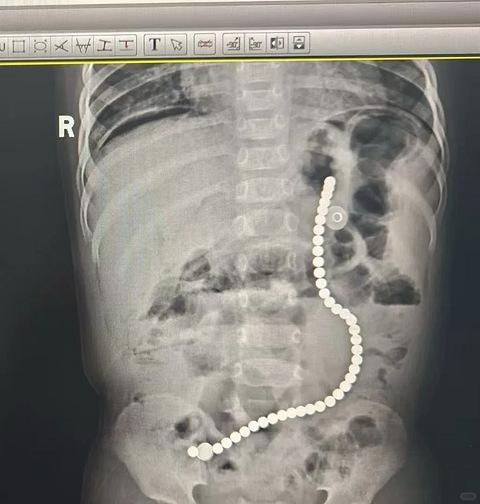

家里有宝宝,一定一定不要给买这个……

希望能被更多宝妈宝爸们刷到,别在家里出现这种磁力珠。希望尽早出台相关文件,禁止这类产品流入商品市场。 今天,医院收治一例儿童吞服磁力珠后出现肠穿孔,通过急诊手术取出磁力珠……每年都有好多宝宝吞服这个磁力珠来急诊手术的。